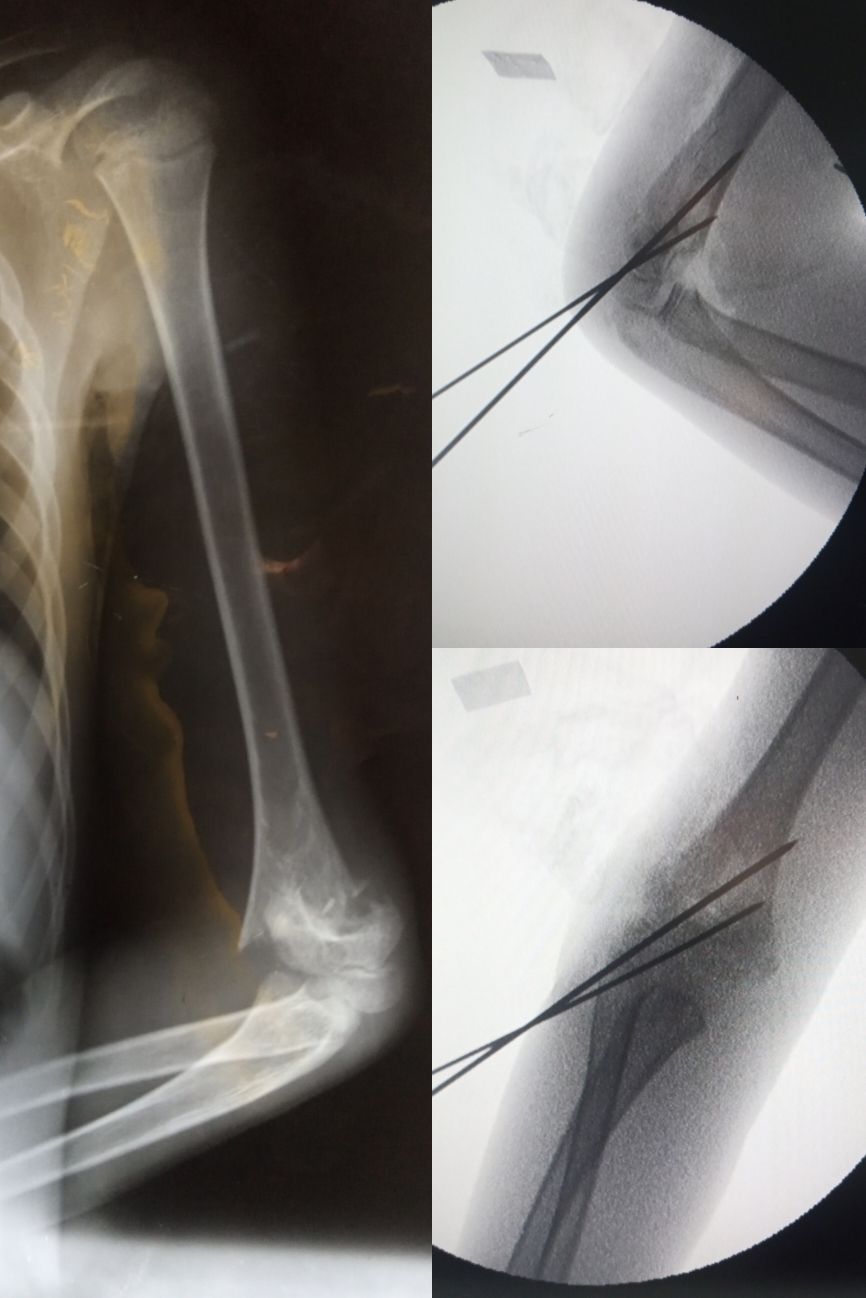

Supracondylar Fx of humerus

Trauma

Orthopaedics

Kwiring